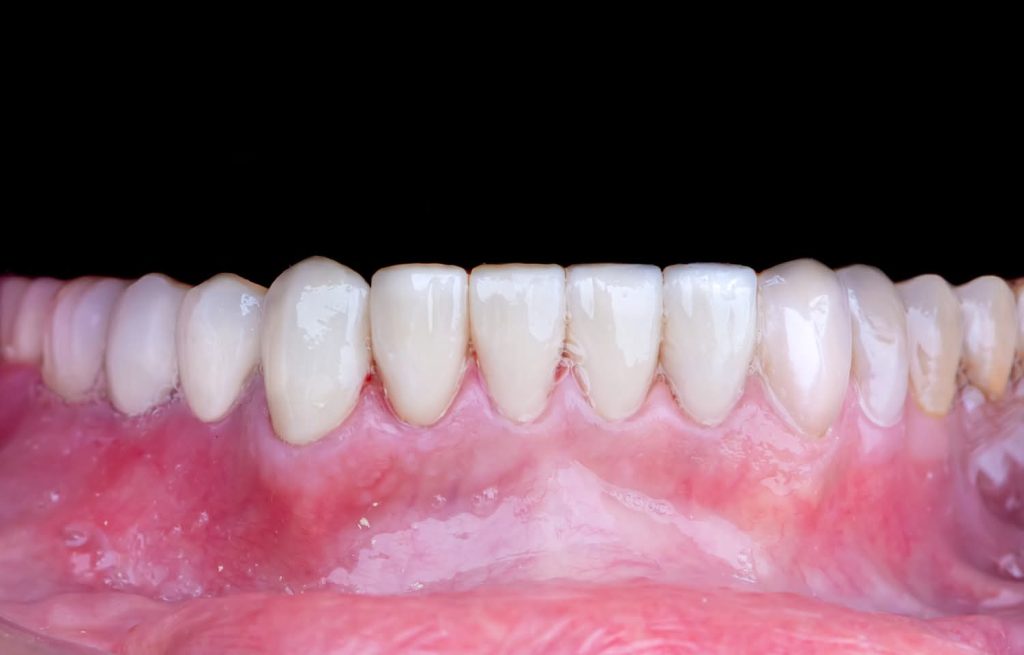

3. Definitive Phase:

This phase began with the upper arch:

Placement of implants in the free-end areas.

Preparation of teeth and insertion of the fixed prosthesis.

The lower arch was managed similarly to the upper arch.

The patient has now been under follow-up for nearly 4 years and remains very happy and comfortable.